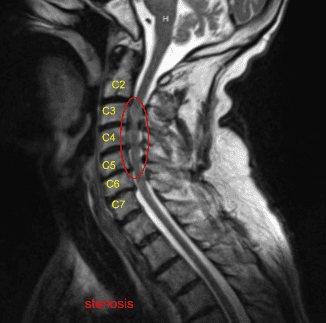

Se realizó una resonancia magnética que encontró estenosis grave en C3-4 con estenosis moderada a severa en C4-5 y C5-6. La Dra. Mariwalla y yo discutimos las opciones de tratamiento y el paciente optó por el manejo quirúrgico. Hablamos de la necesidad de discectomía cervical anterior y la colocación de jaulas y tornillos.